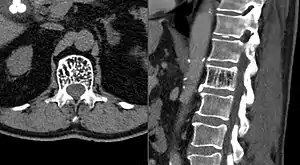

Axial and sagittal CT views of a vertebral hemangioma

On computed tomography (CT) or radiograph, VHs can cause rarefaction with vertical striations (often referred to as corduroy pattern) or a coarse honeycomb appearance. A polka-dot appearance on CT scan represents a cross-section of reinforced trabeculae.[11][13] CT best defines the bony architecture and is the best diagnostic imaging method.[14]